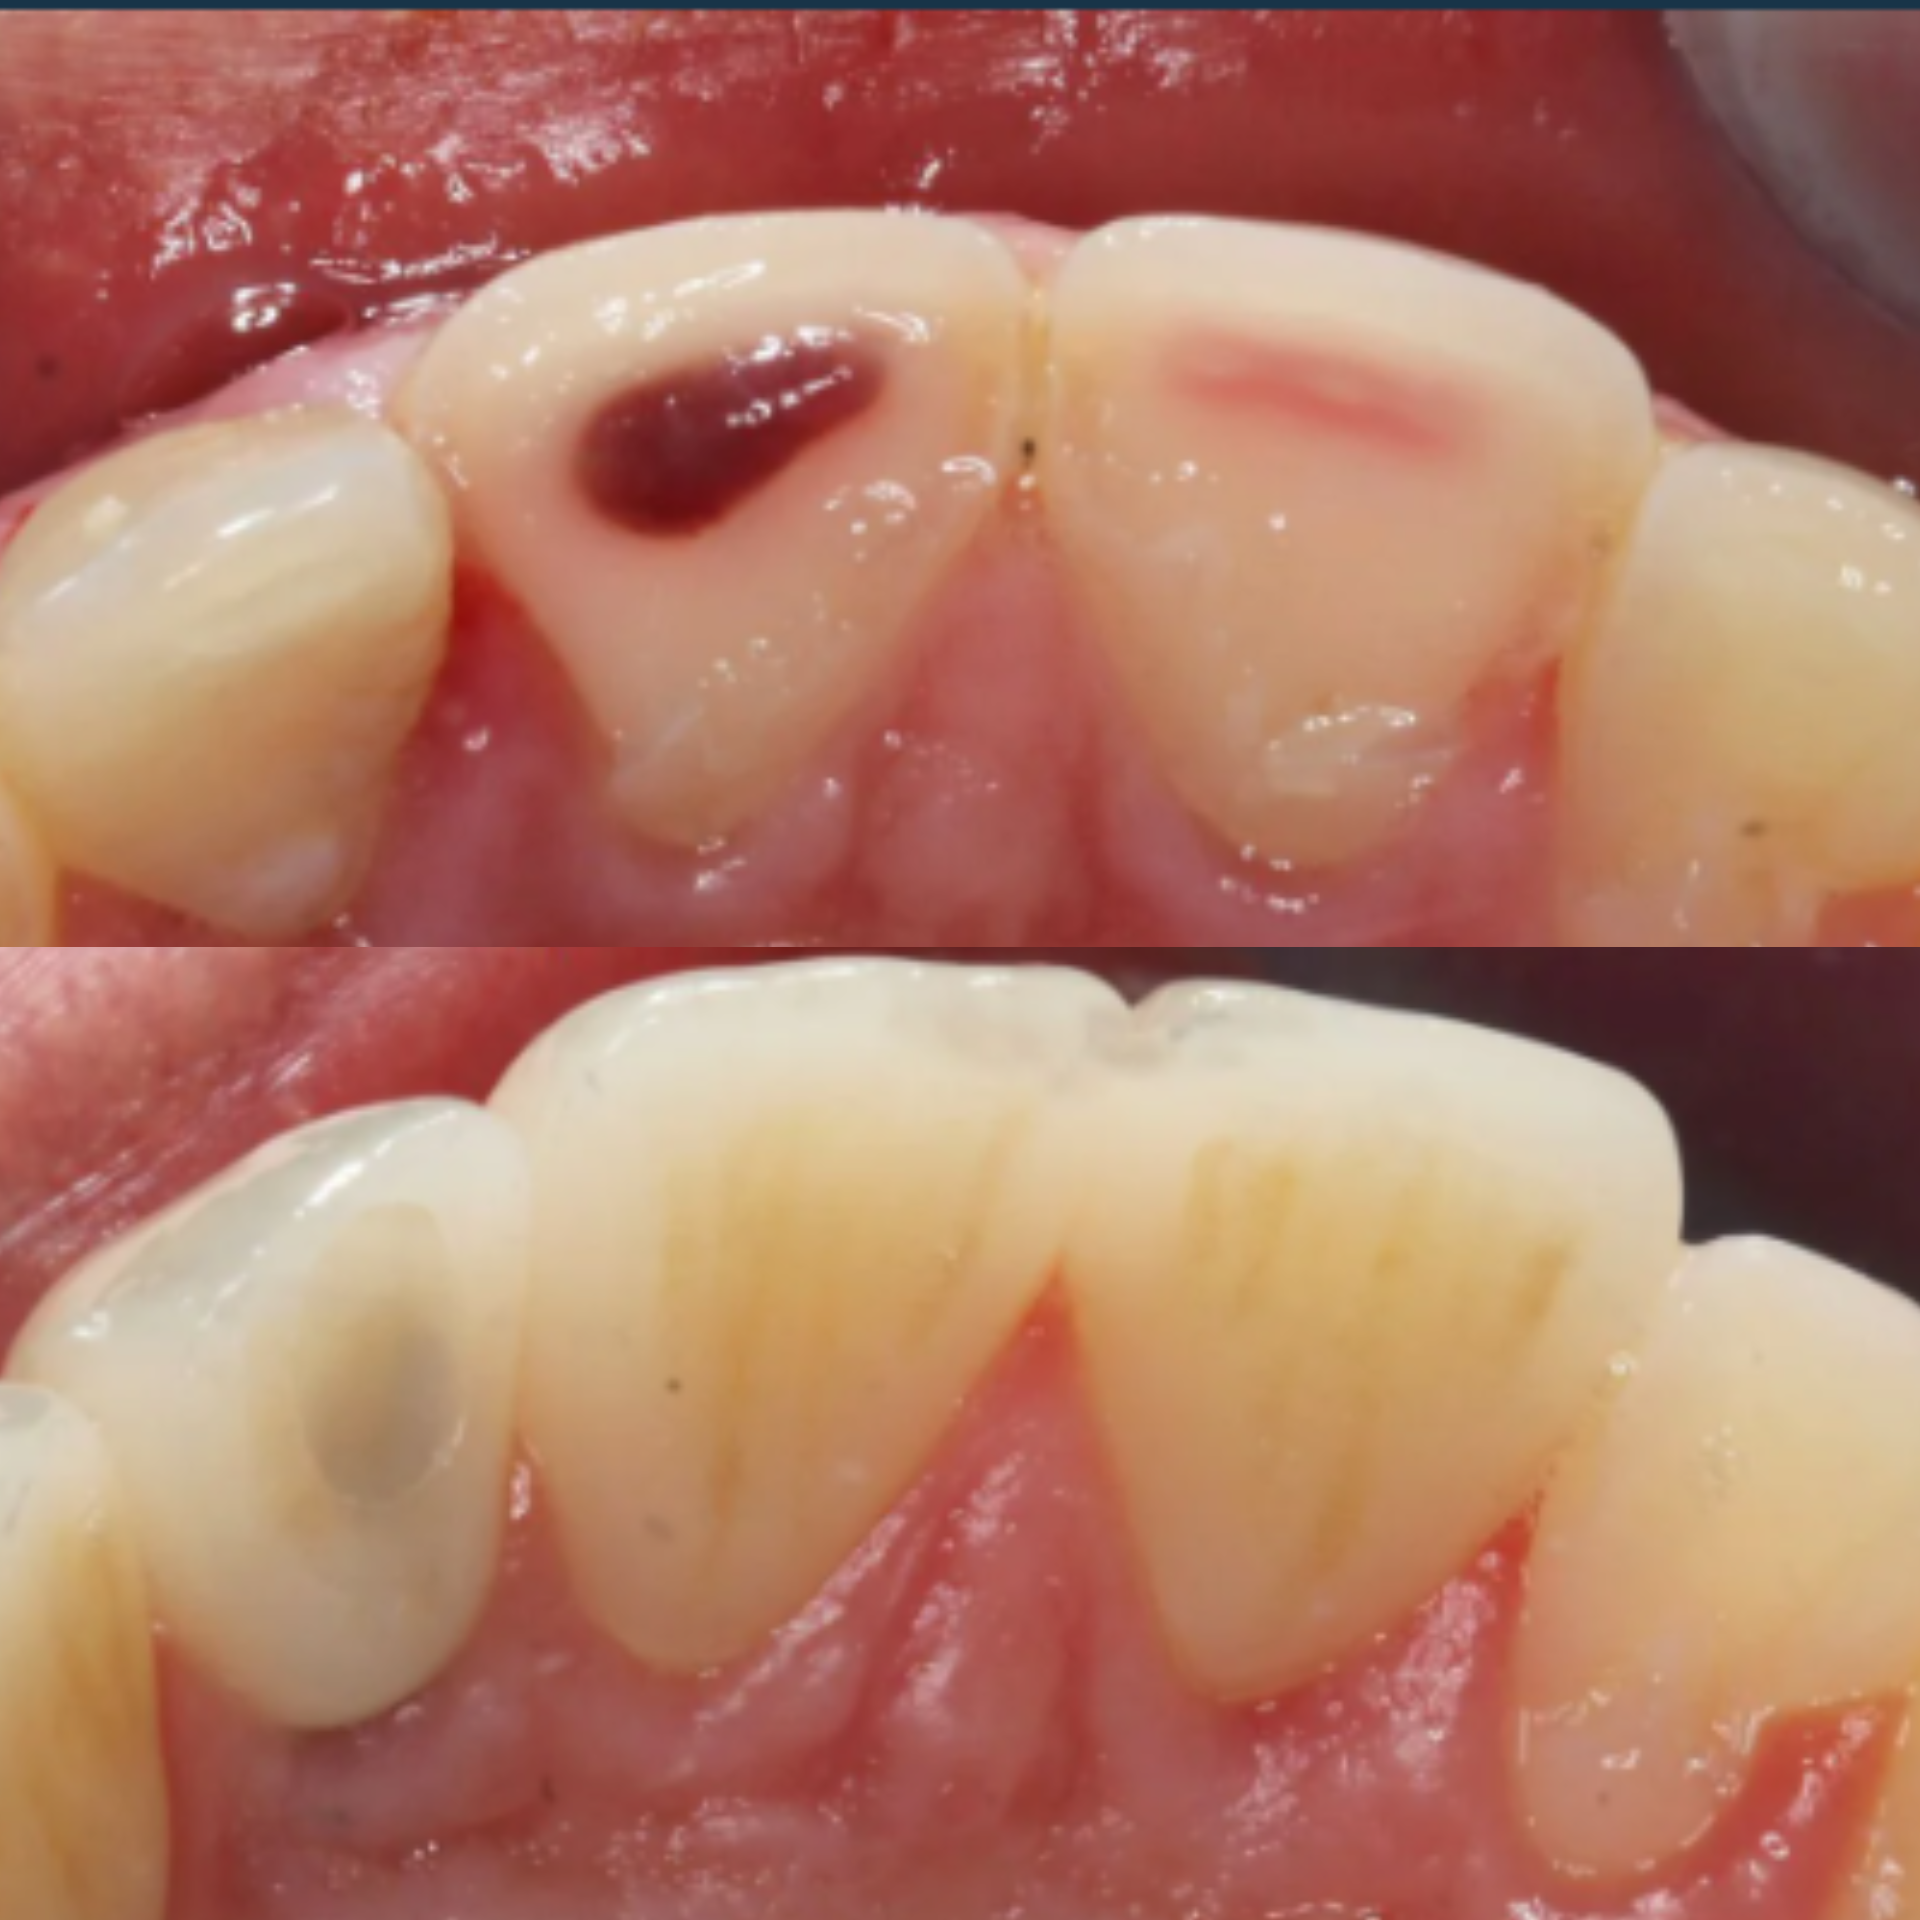

At our practice, we recently helped a patient restore their smile after experiencing a complex dental issue involving a periodontal infection and a root fracture. To fully restore both health and aesthetics, we recommended a comprehensive implant-based solution.

The treatment process included:

• Extraction and Bone Grafting to properly prepare the site for implant placement

• Implant Placement with Soft Tissue Grafting to ensure long-term stability and natural-looking gum contours

• Provisional Implant-Supported Crown to maintain appearance and function during healing

• Final Implant-Supported Crown, custom-designed for strength, beauty, and seamless integration

We are extremely proud of the final result, and most importantly, our patient is now enjoying a healthy, confident smile once again.